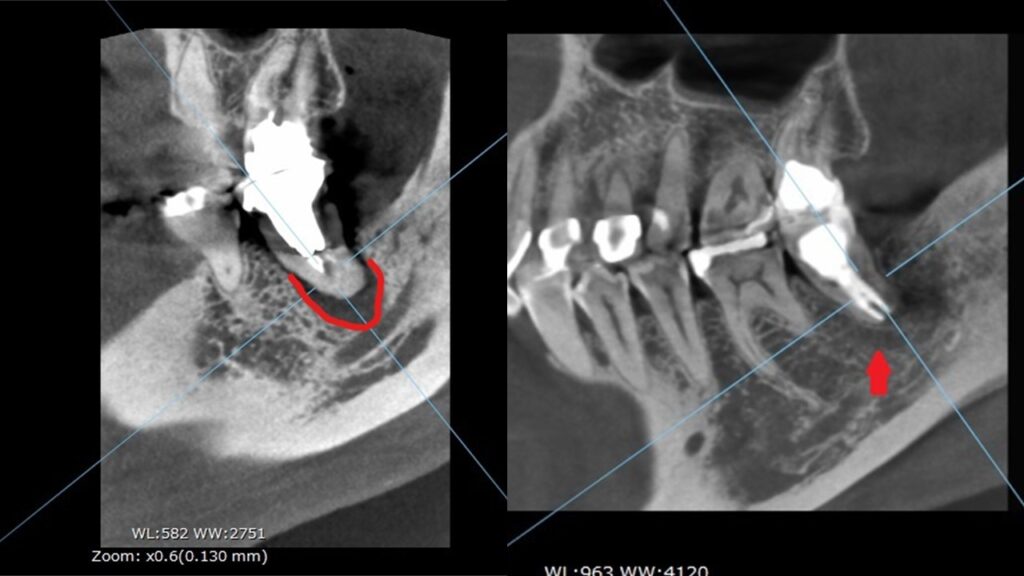

CT撮影の画像です。

CT撮影は、様々な方向から歯を立体的に確認することができます。

つまり3Dですね。

輪切り方向から見ても、

正面から見ても、赤枠の場所が黒く抜けています。

CT撮影で、膿んで骨が溶けている範囲が詳細に分かります。